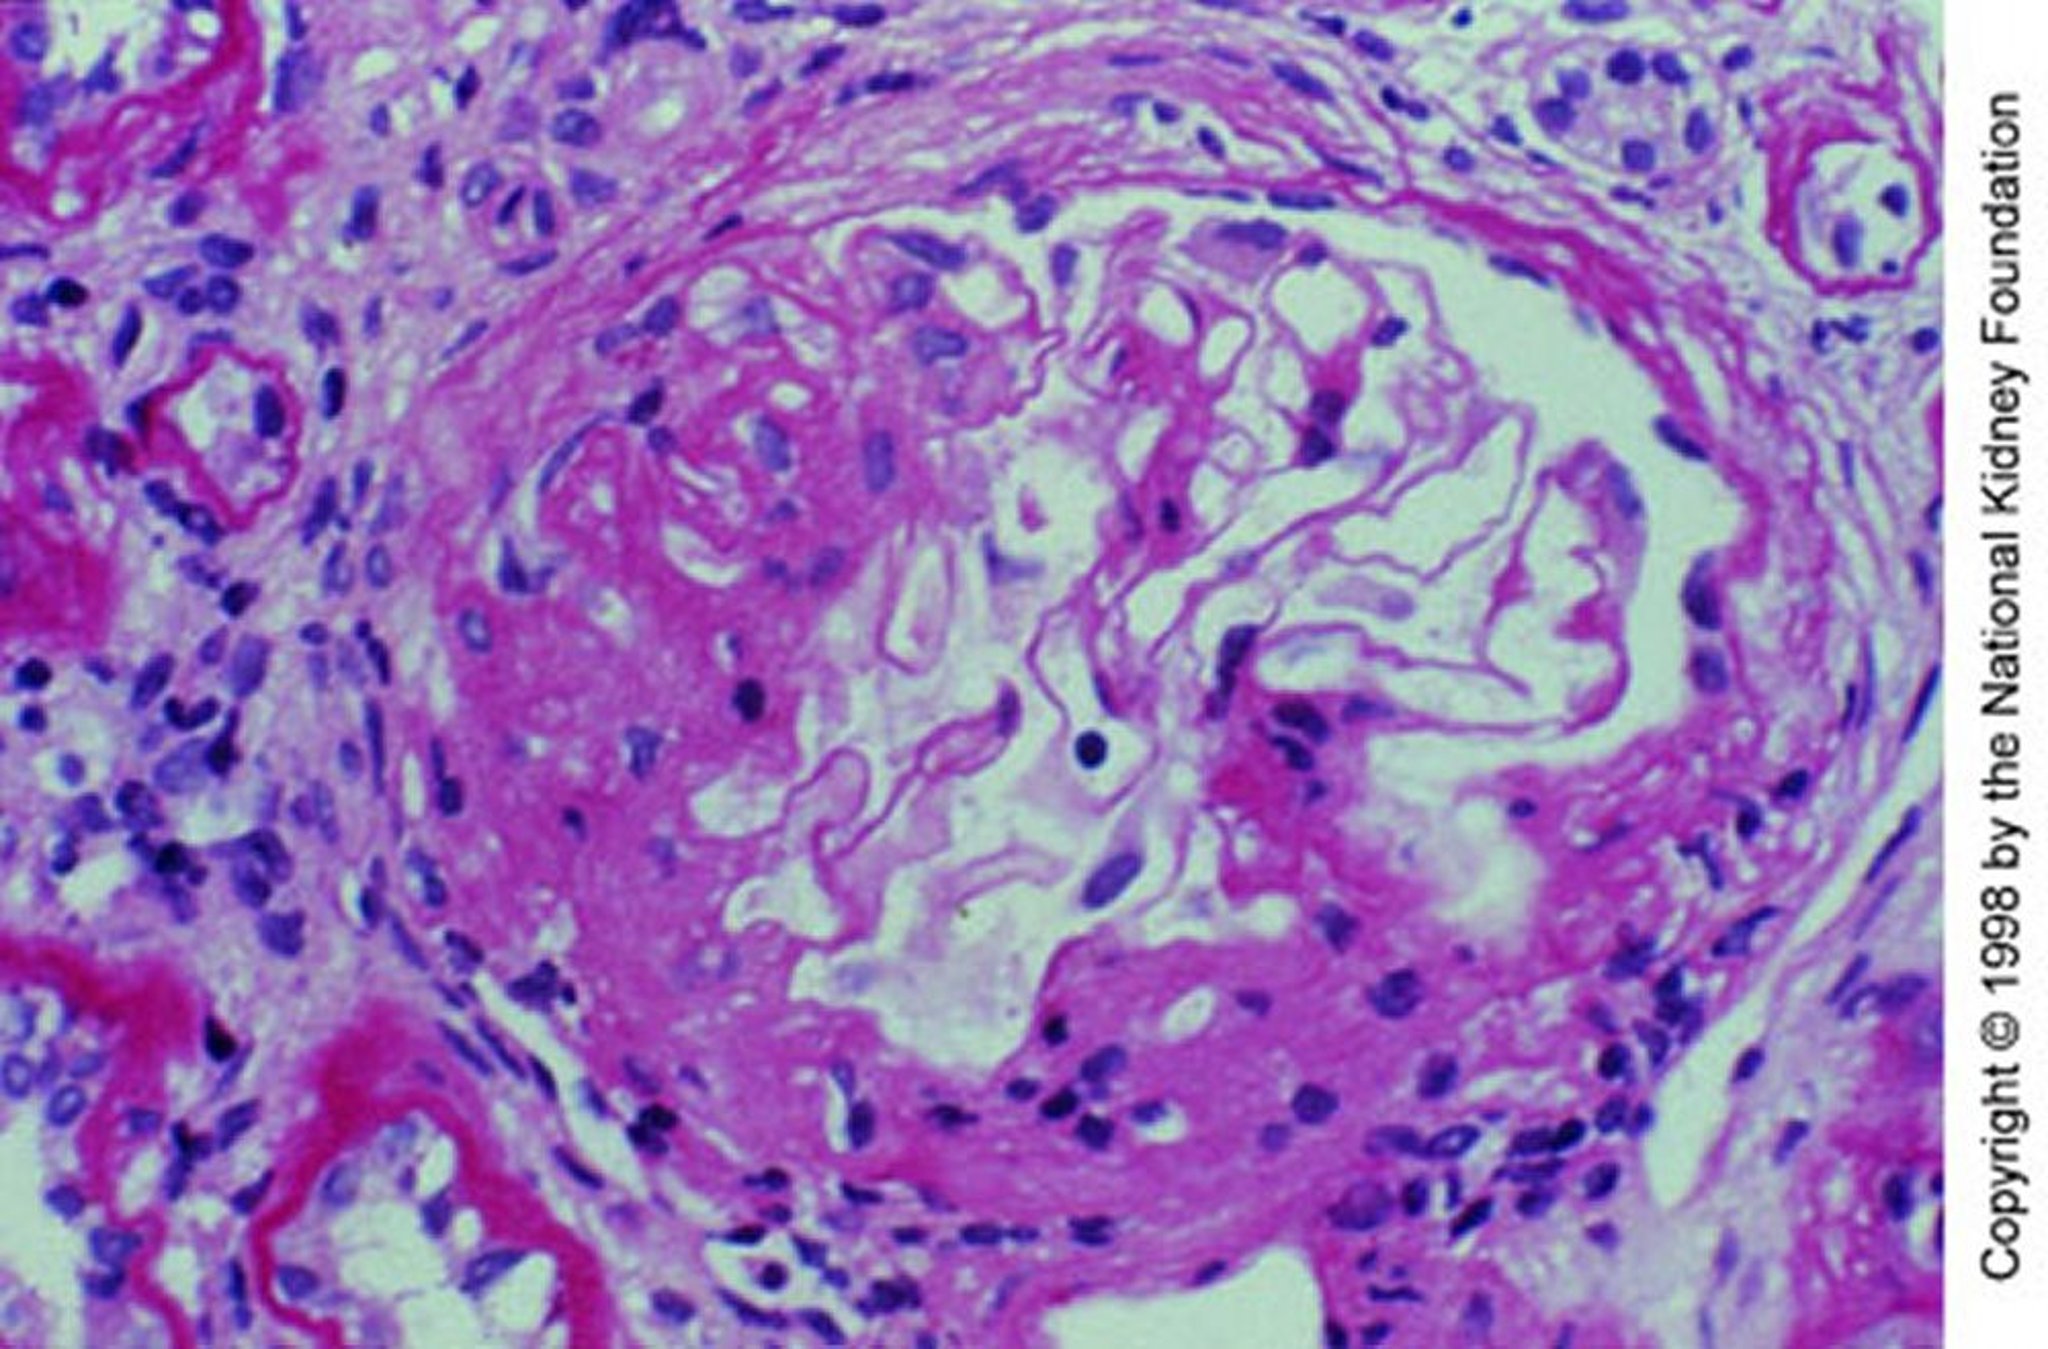

Nefropatía por IgA (expansión mesangial)

Expansión mesangial con esclerosis segmentaria (tinción con ácido peryódico de Schiff, ×200).

Image provided by Agnes Fogo, MD, and the American Journal of Kidney Diseases' Atlas of Renal Pathology (véase www.ajkd.org).